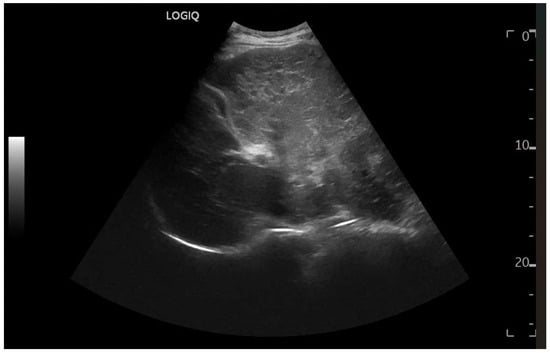

Ultrasound imaging is capable of identifying heterogeneous echotexture and hepatomegaly, which are early indicators of congestive hepatopathy [46]. Several studies have shown correlations between the extent of sonographic abnormalities and the severity of hepatic fibrosis or cirrhosis [36,47,48]. The most common ultrasound findings encompass a nodular hepatic surface, right-lobe volume reduction, smooth-to-rounded contour changes, and irregular outer profiles [49,50,51] (Figure 2). The echotexture appears granular and markedly heterogeneous, with hyperechogenic nodules of varying sizes [49,50,51] (Figure 3, Figure 4, Figure 5, Figure 6, Figure 7 and Figure 8).

Figure 7.

Hypotrophy of the right lobe. Nodular profiles. Markedly heterogeneous echostructure, with increased fibrous component and fibrous trabeculae delimiting pseudo-nodular areas, within the context of a vascular-type cirrhosis.

A cohort analysis involving 55 individuals who had undergone the Fontan procedure demonstrated that 67% displayed irregular hepatic echotexture or surface nodularity, changes that showed a temporal association with the duration since surgery. Severe congestion with PHTN may present with dilated portal veins (diameter > 13 mm), enlarged paraumbilical veins, collateral circulation, splenomegaly (Figure 9), ascites, and reversal of portal vein flow [50,52,53].